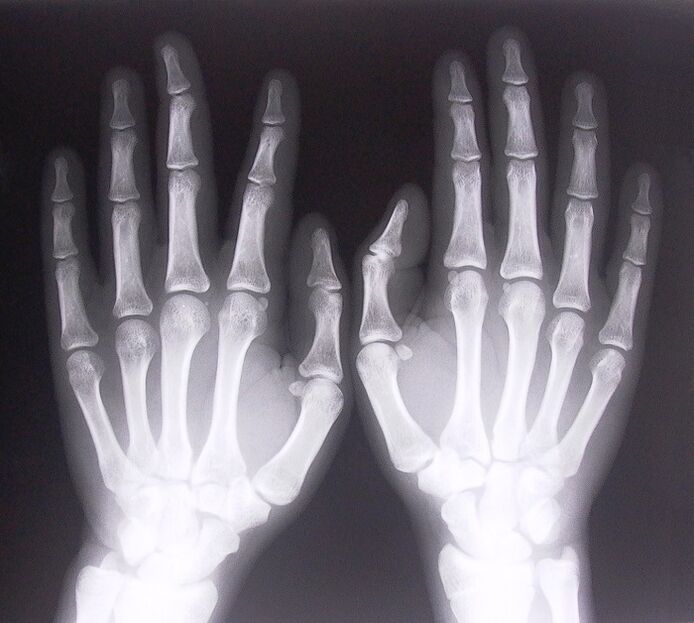

- Stenosing ligamentitis.To identify the cause of the disease, it is necessary to undergo an x-ray.Symptoms are typical: painful hand movements, tight curvature of the palm.In addition, clicks are often heard during extension.

- Take x-rays.